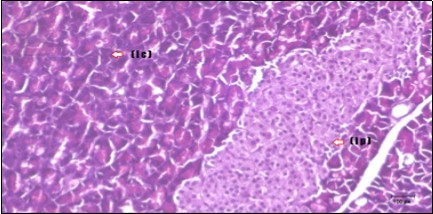

Pancreas Histopathological Observations

Histological examination of pancreas of the control rats showed normal sized islets of pancreas (Ip) compared to the diabetic rats which showed markedly atrophic islets of pancreas (I.p.) (Figure 8 and Figure 9). Pancreas of in groups (3) and (4) rats showed mild atrophic islets of pancreas (I.p.) with inflammatory cellular infiltrate (Figure 10 and Figure 11). The pancreas of rats in group (5) showed nearly normal islets of pancreas (I.p.) with few inflammatory cellular infiltrate (I.c.) (Figure 12).

Figure 12.Photomicrogragh of pancreas section of treated rat with both Fenugreek and Glimepiride showing nearly normal islets of Langerhans with spindle (arrow) & polygonal cells (dashed- arrow). (H&E) (40x).

Histopathological observation in diabetic control showed degenerative changes in both endocrine and exocrine pancreases. A probable explanation may be related to oxidative stress resulting from hyperglycemia which decreases the antioxidants levels and increases ROS 33 and the activities of antioxidant enzyme were altered in diabetic rats. These effects further exacerbate the development and progression of diabetes complications and these may represent the causes of degeneration revealed in histological sections. Fenugreek improved blood glucose levels and insulin, lowered pancreatic islet and β-cells damage which may be attributed to its immune modulatory activity and insulin stimulation action along with its antioxidant potential 32. Glimepiride caused restoration of morphology of beta cell of diabetic and it increased percentage of beta cells 34. This protective effect could be attributed to the antioxidant properties of Glimepiride. Combination therapy improves the protective effect of both therapies alone.